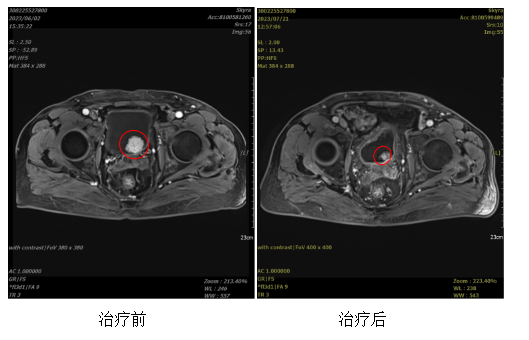

患者,男,70岁,膀胱尿路上皮癌,分期:rcT2bN0M1b IVB期